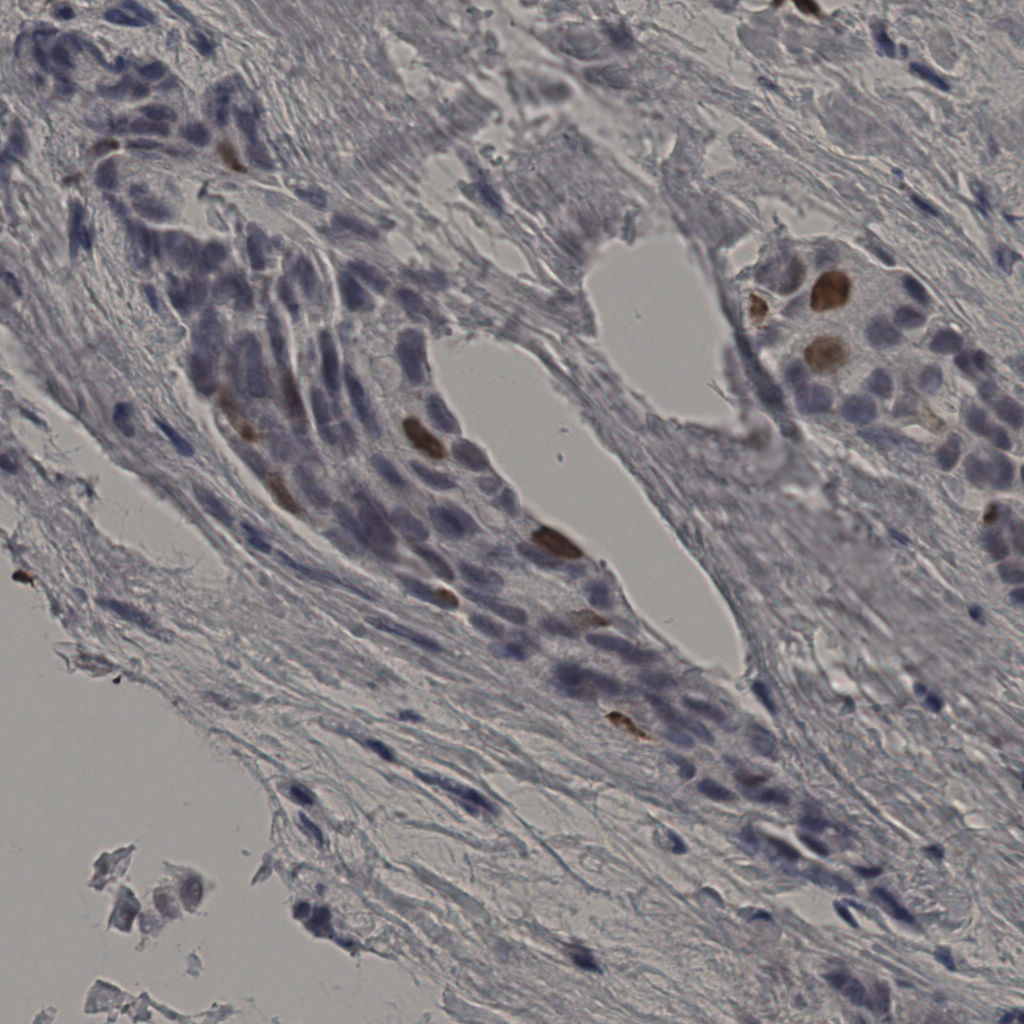

5.31%

Ki67 指数

阴 19502

阳 1093